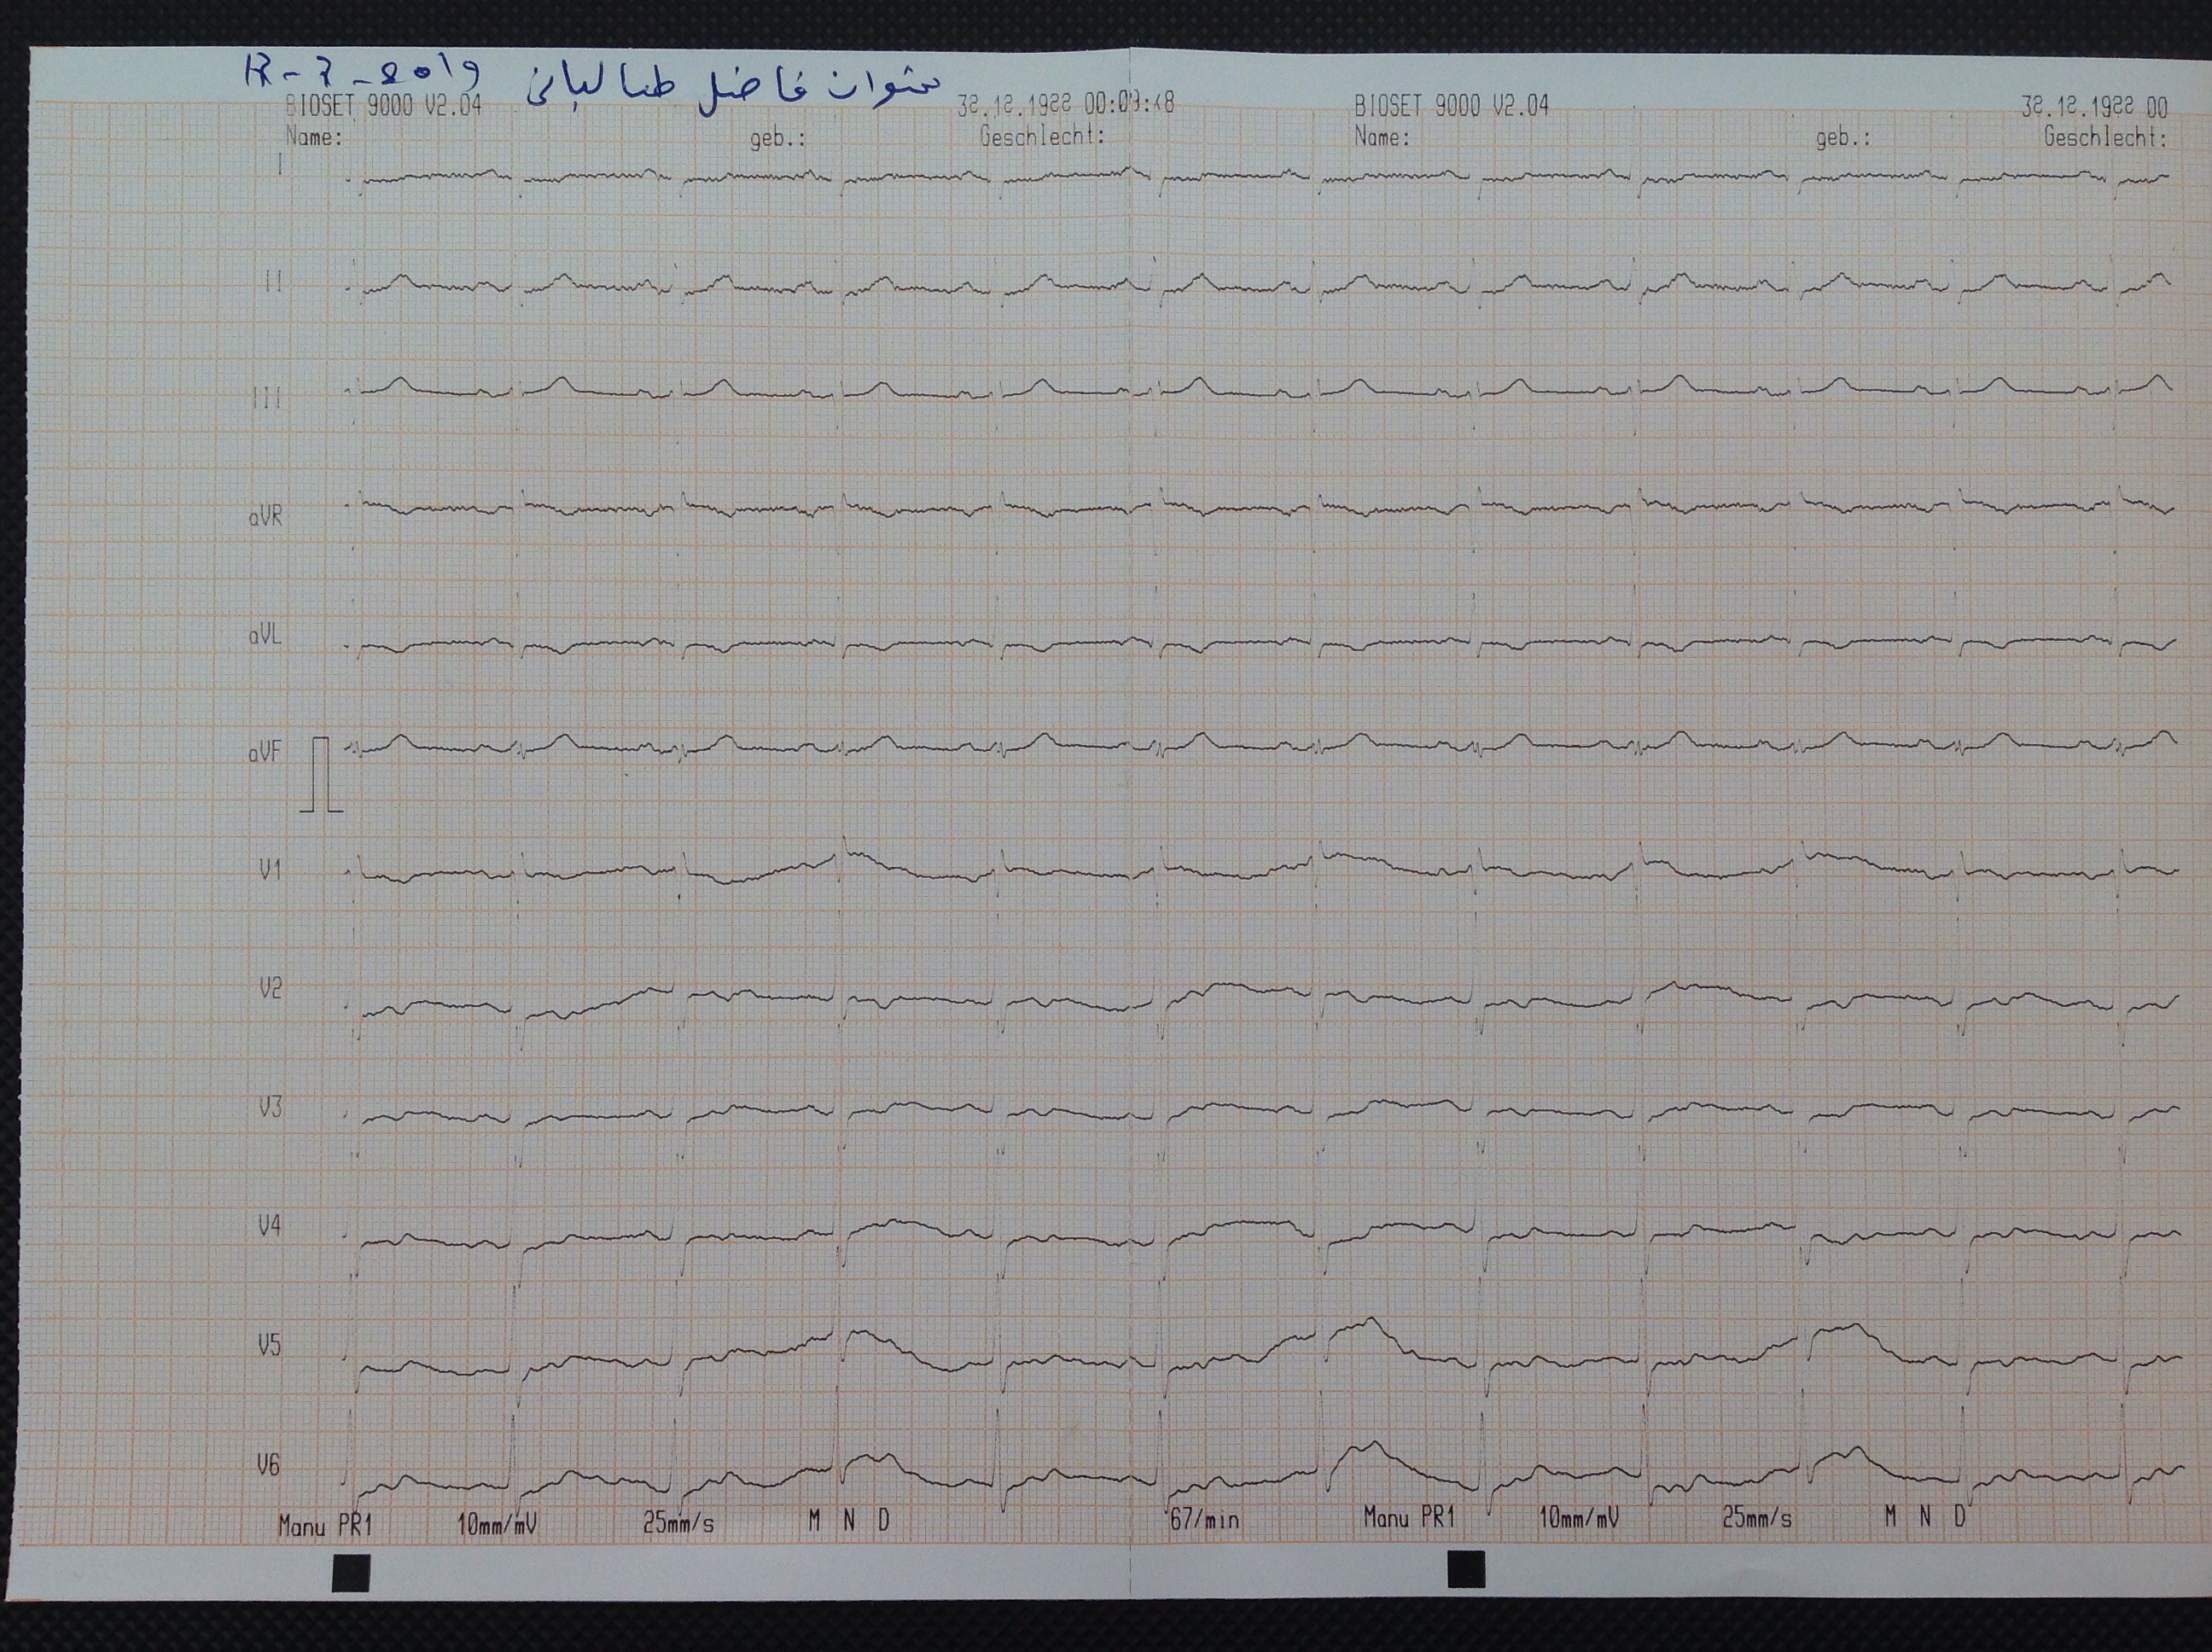

ID : 589      SHWAN FAZEL TALABANI           1953             Male      W : 116 kg     H : 175 cm         Angio        PCI        CABG        HTN             HPI :

BP : 146/99     PR : 71     RR :     SPO2 : 95     CC : FOLLOW UP